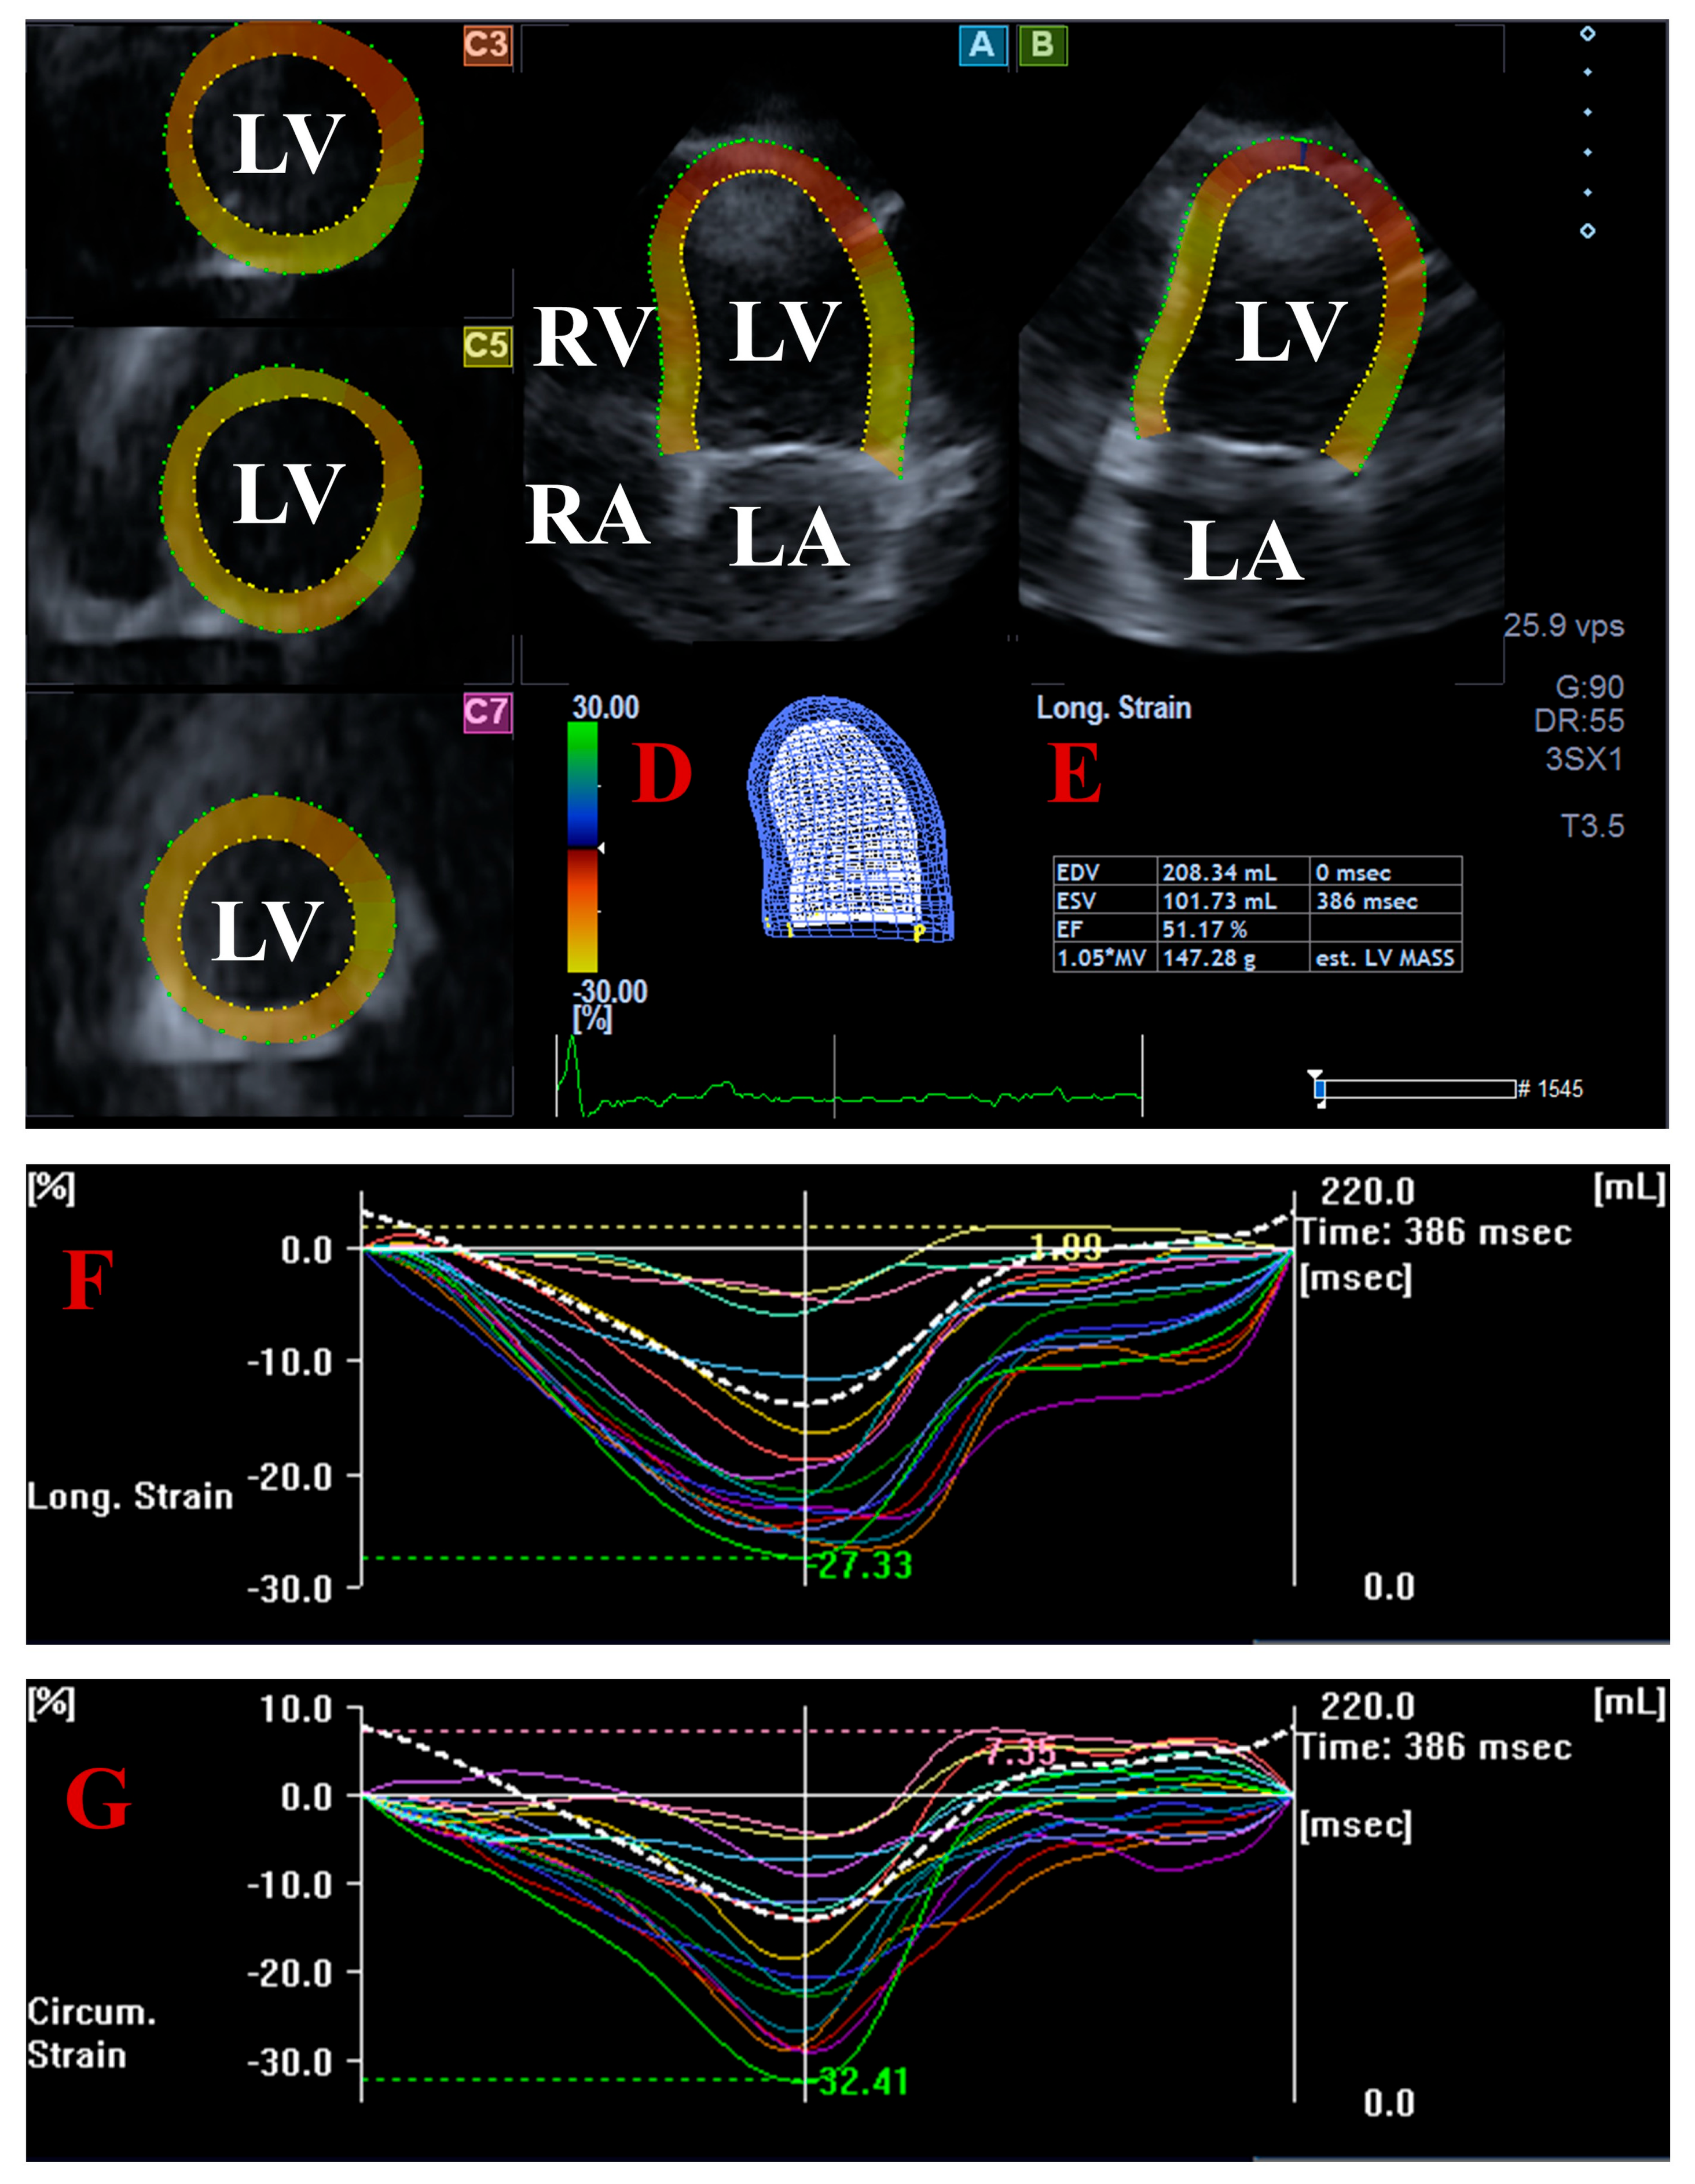

2.3. Three-Dimensional Speckle-Tracking Echocardiography

3.3. Three-Dimensional Speckle-Tracking Echocardiography